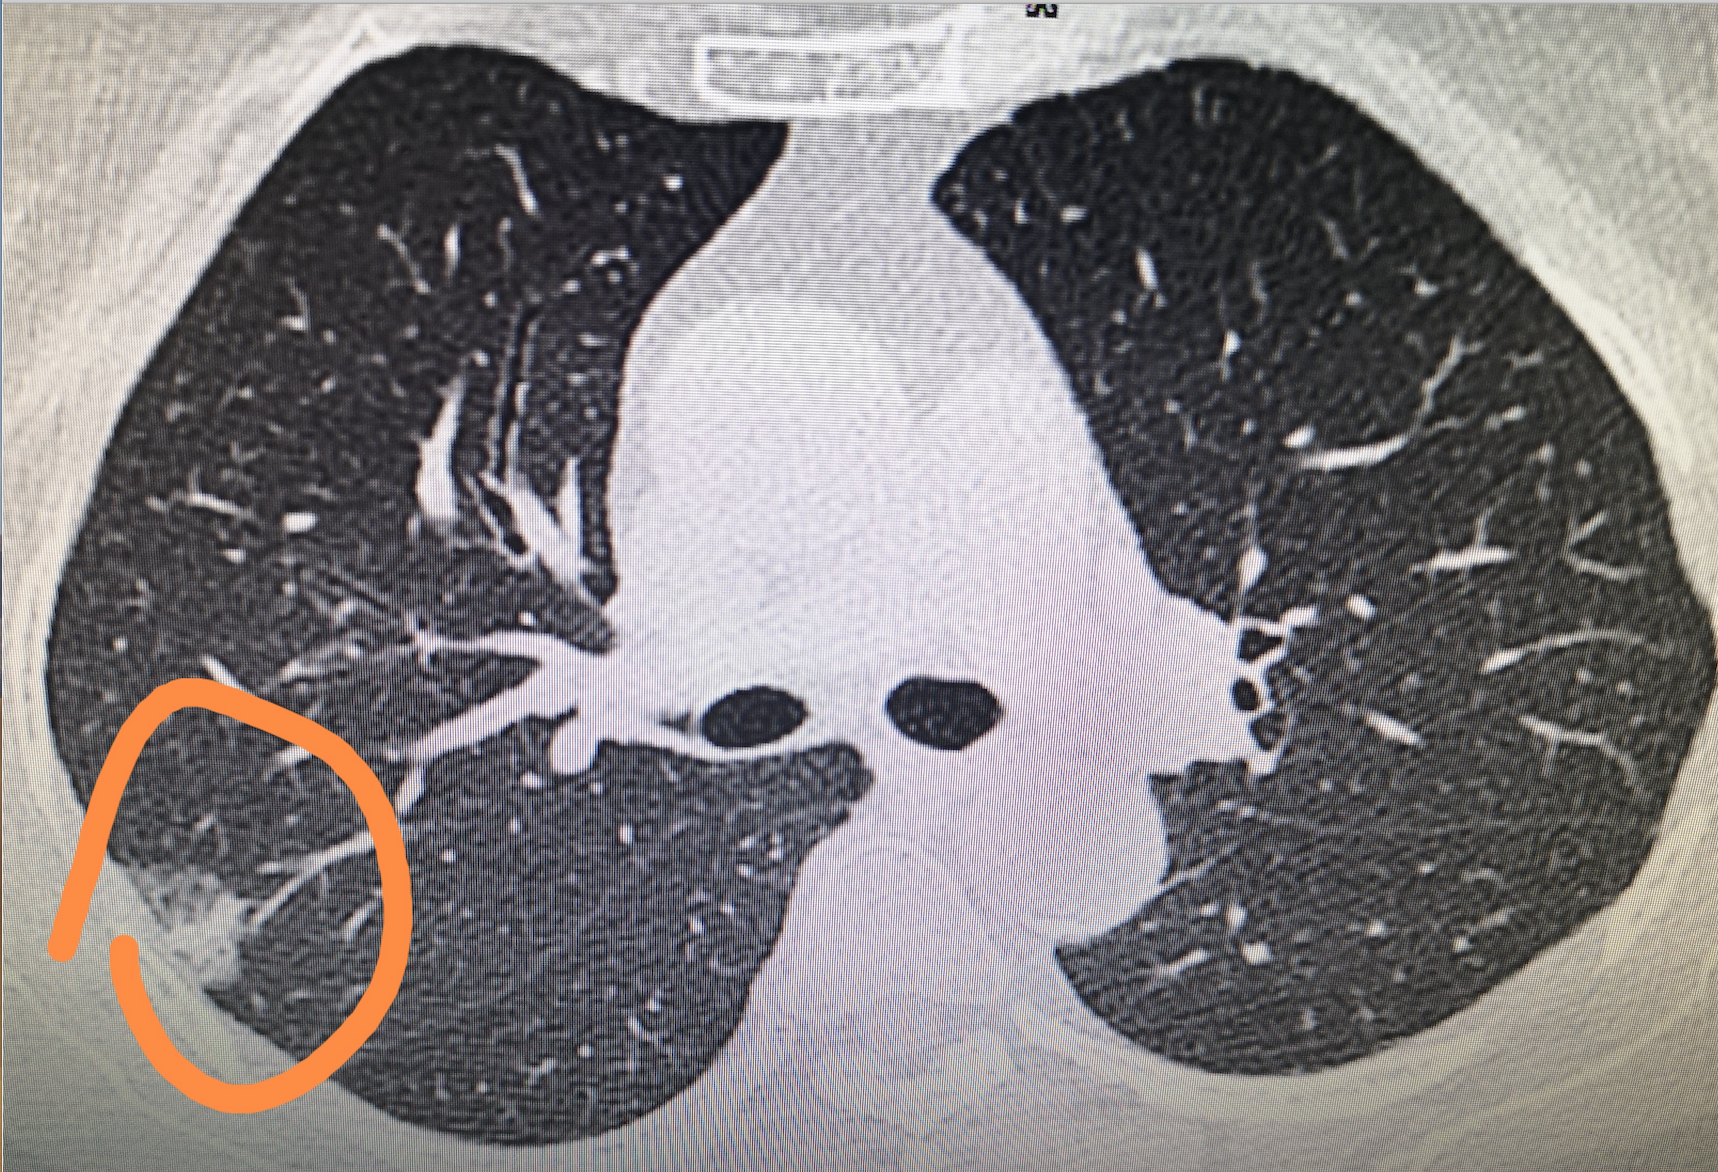

症状和体征因发作的严重程度和受累器官的数量而异。在胸内结节病的早期阶段,通常没有明显的症状。有时有咳嗽、少量痰,有时有少量咯血;可能会出现疲劳、发烧、盗汗、食欲不振和体重减轻。

病变广泛时可出现胸闷、气短,甚至紫绀。合并感染、肺气肿、支气管扩张、肺心病等可加重。